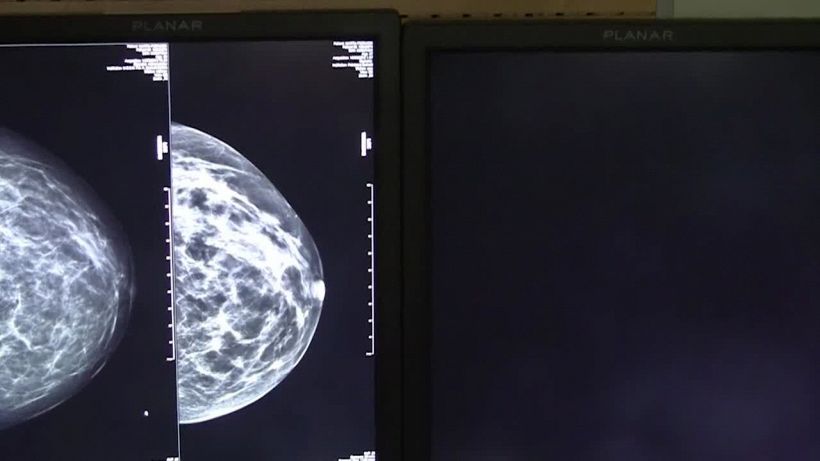

Torna a salire la spesa privata per le cure: +9% nel 2021

Rapporto Crea, aumentano anche le rinunce. Disagi economici per 1,3 milioni di famiglie